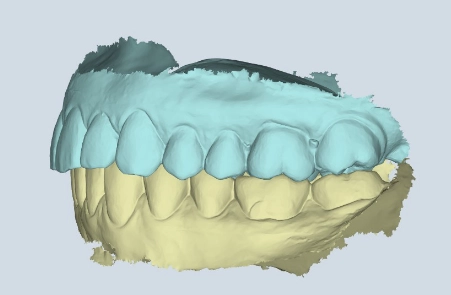

Mit der digitalen 4D-Funktionsdiagnostik erfassen wir Ihren Biss und die Kiefergelenkfunktion in Bewegung, um intelligentere und stabilere Behandlungen zu planen – besonders bei CMD und komplexen Fällen.

Mit unserer digitalen Funktionsanalyse erfassen wir Ihre Kieferfunktion in 4D-Bewegung, um Behandlungen zu entwickeln, die sich genauso gut anfühlen wie sie aussehen. Schnell und strahlungsfrei – für detaillierte Einblicke in Biss, Kiefergelenke und Kaufunktion in Echtzeit und in Zeitlupe.

Sehen Sie genau, wie sich Ihr Unterkiefer in Echtzeit bewegt – und Probleme entdecken, die statische Messungen übersehen.

Bevor eine Behandlung beginnt, nutzen wir das Echtzeit-Kiefertracking, um genau zu sehen, wie Ihr gesamter Kauapparat in Bewegung funktioniert.

Wir beginnen mit einer digitalen 4D-Funktionsdiagnostik, um zu erfassen, wie sich Ihr Kiefer in Echtzeit bewegt. Schnell, berührungslos und strahlungsfrei – für einen vollständigen Blick auf Biss, Gelenke und Funktion. Kein Rätselraten. Nur Klarheit.

Jedes Lächeln erzählt eine Geschichte – und Ihr Kiefer auch. Mit unserer digitalen 4D-Diagnostik sehen Sie, wie Ihr gesamter Kauapparat funktioniert, bevor wir starten – und was wir verbessern sollten.